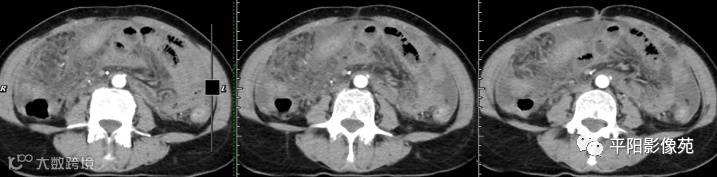

腹部增强 动脉期